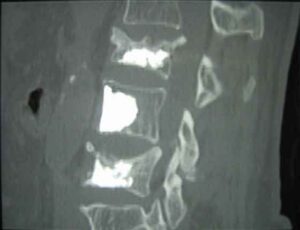

osteoprotico